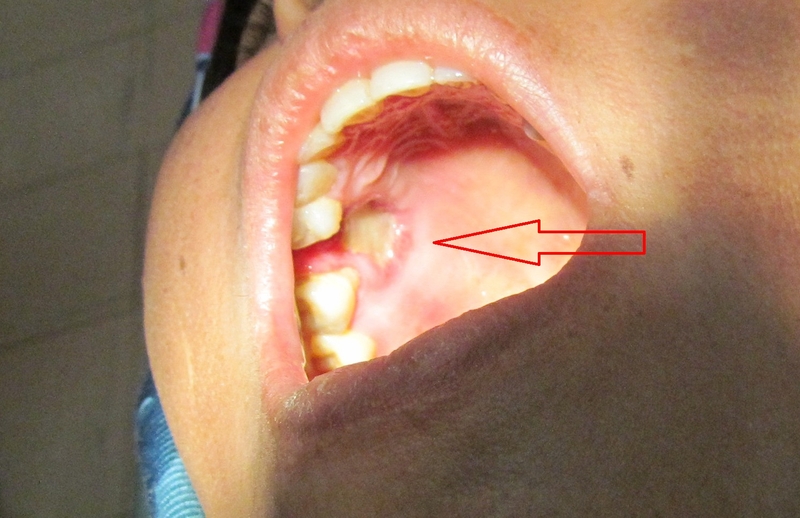

Dấu hiệu hoại tử xương hàm hậu Covid ở mỗi bệnh nhân sẽ khác nhau, tùy mức độ nghiêm trọng của tình trạng hoại tử. Tuy nhiên, quan sát các bệnh nhân bị hoại tử xương hàm sau khi mắc Covid, các bác sĩ ghi nhận các triệu chứng cơ bản như:

Dưới đây là những triệu chứng mà hầu hết bệnh nhân hoại tử xương hàm do Covid đều gặp phải:

Phần xương hàm bị hoại tử nếu không được phẫu thuật loại bỏ sẽ trở thành nơi khu trú lý tưởng của vi khuẩn và có thể gây ra sốc nhiễm trùng hoặc nhiễm trùng huyết đe dọa tính mạng. Bệnh hoại tử xương hàm hậu Covid cần chữa trị kịp thời để khống chế tiến triển của tình trạng hoại tử và giảm nguy cơ biến chứng.

Nguyên tắc trong điều trị hoại tử xương hàm do Covid là phẫu thuật loại bỏ phần xương bị hoại tử. Sau đó sẽ tấn công bằng các thuốc kháng nấm, kháng sinh ít nhất 3 tuần và theo dõi nguy cơ tái phát. Bệnh nhân thậm chí có thể phải dùng kháng sinh, kháng nấm đến 6 tháng. Sau khi tình trạng bệnh ổn định, bác sĩ sẽ cân nhắc việc tái tạo, phục hình xương.